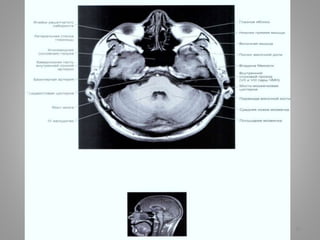

Великі цистерни головного мозку

• Велика (мозочково-мозкова) цистерна (cisterna magna, c. cerebellomedullaris) –

• Цистерна моста (препонтинна) - розташовується наперед від моста мозку, містить

базилярну артерію. Зєднується позаду з мосто-мозочково-мозковою цистерною та

субарахноідальним простором спинного мозку, попереду – з міжніжковою

цистрною.

• Базальна цистерна (c. suprasellar) має п'ятикутну форму, включає міжніжкову

цистерну (між ніжками мозку) і цистерну перехреста (між перехрестом зорових

нервів і лобними частками).

• Чотиригорбкова цистерна (вени Галена) (c. quadrigeminalis) розташовується між

мозолистим тілом і мозочком; у її ділянці можуть розташовуватись

субарахноідальні кисти

• Обвідна (охоплююча; по Синельникову - обхідна) цистерна (c. ambient) - канал

неправильної форми, що проходить по бокам ніжок мозку і даху середнього

мозку; сполучається з мостовою і міжніжковою цистернами спереду і

чотирегорбиковою цистерною ззаду.

• Цистерна бічної ямки великого мозку (cisterna fossae lateralis cerebri) -

розташовується в латеральній борозні великого мозку.

9